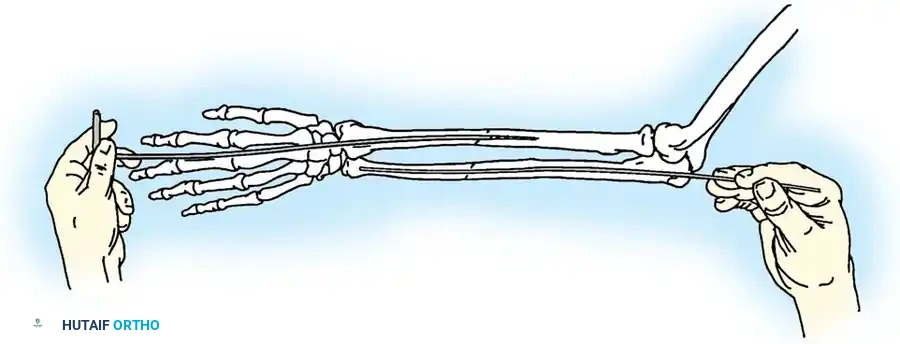

Fractures of the forearm bones in adults frequently demand surgical intervention to restore the complex biomechanics of the upper extremity. Surgical indications encompass fractures of the olecranon, the head or neck of the radius, and the proximal third of the ulna associated with dislocation of the radial head (Monteggia lesions). Furthermore, operative management is routinely indicated for isolated displaced fractures of the ulnar or radial shafts, as well as diaphyseal fractures involving both bones.

The primary goal of surgical intervention in the forearm and elbow is the exact restoration of anatomical alignment, axial length, and rotational stability. In the proximal ulna, the olecranon forms the greater sigmoid notch, articulating with the trochlea of the humerus. Any disruption here not only compromises the extensor mechanism but also threatens the intrinsic stability of the elbow joint.